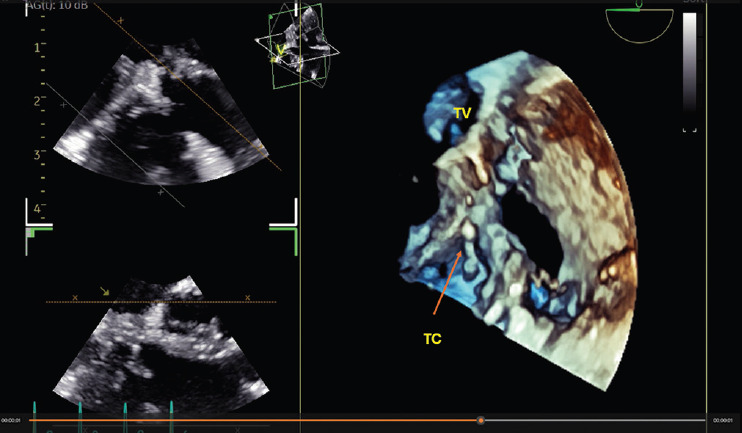

Methods: Recent advancements in the field of miniaturization have led to the development of a new pediatric 3D TEE probe, specifically designed for young children (weight ≥4.5 kg). This probe features a smaller, flexible design and high-spatial and temporal resolution, enabling detailed views of intracardiac structures and real-time imaging crucial for complex diagnosis, planning interventional and surgical procedures. We used this new probe in pediatric cases (weight between 4.5 and 6 kg) with complex congenital heart disease.

Results: In double-outlet right ventricle or in Taussig Bing anomaly the new 3D TEE probe enabled detailed assessment of ventricular septal defect and its relations with tricuspid valve apparatus, and provided details of mitral valve leaflets not detectable by the transthoracic approach, even in small children.